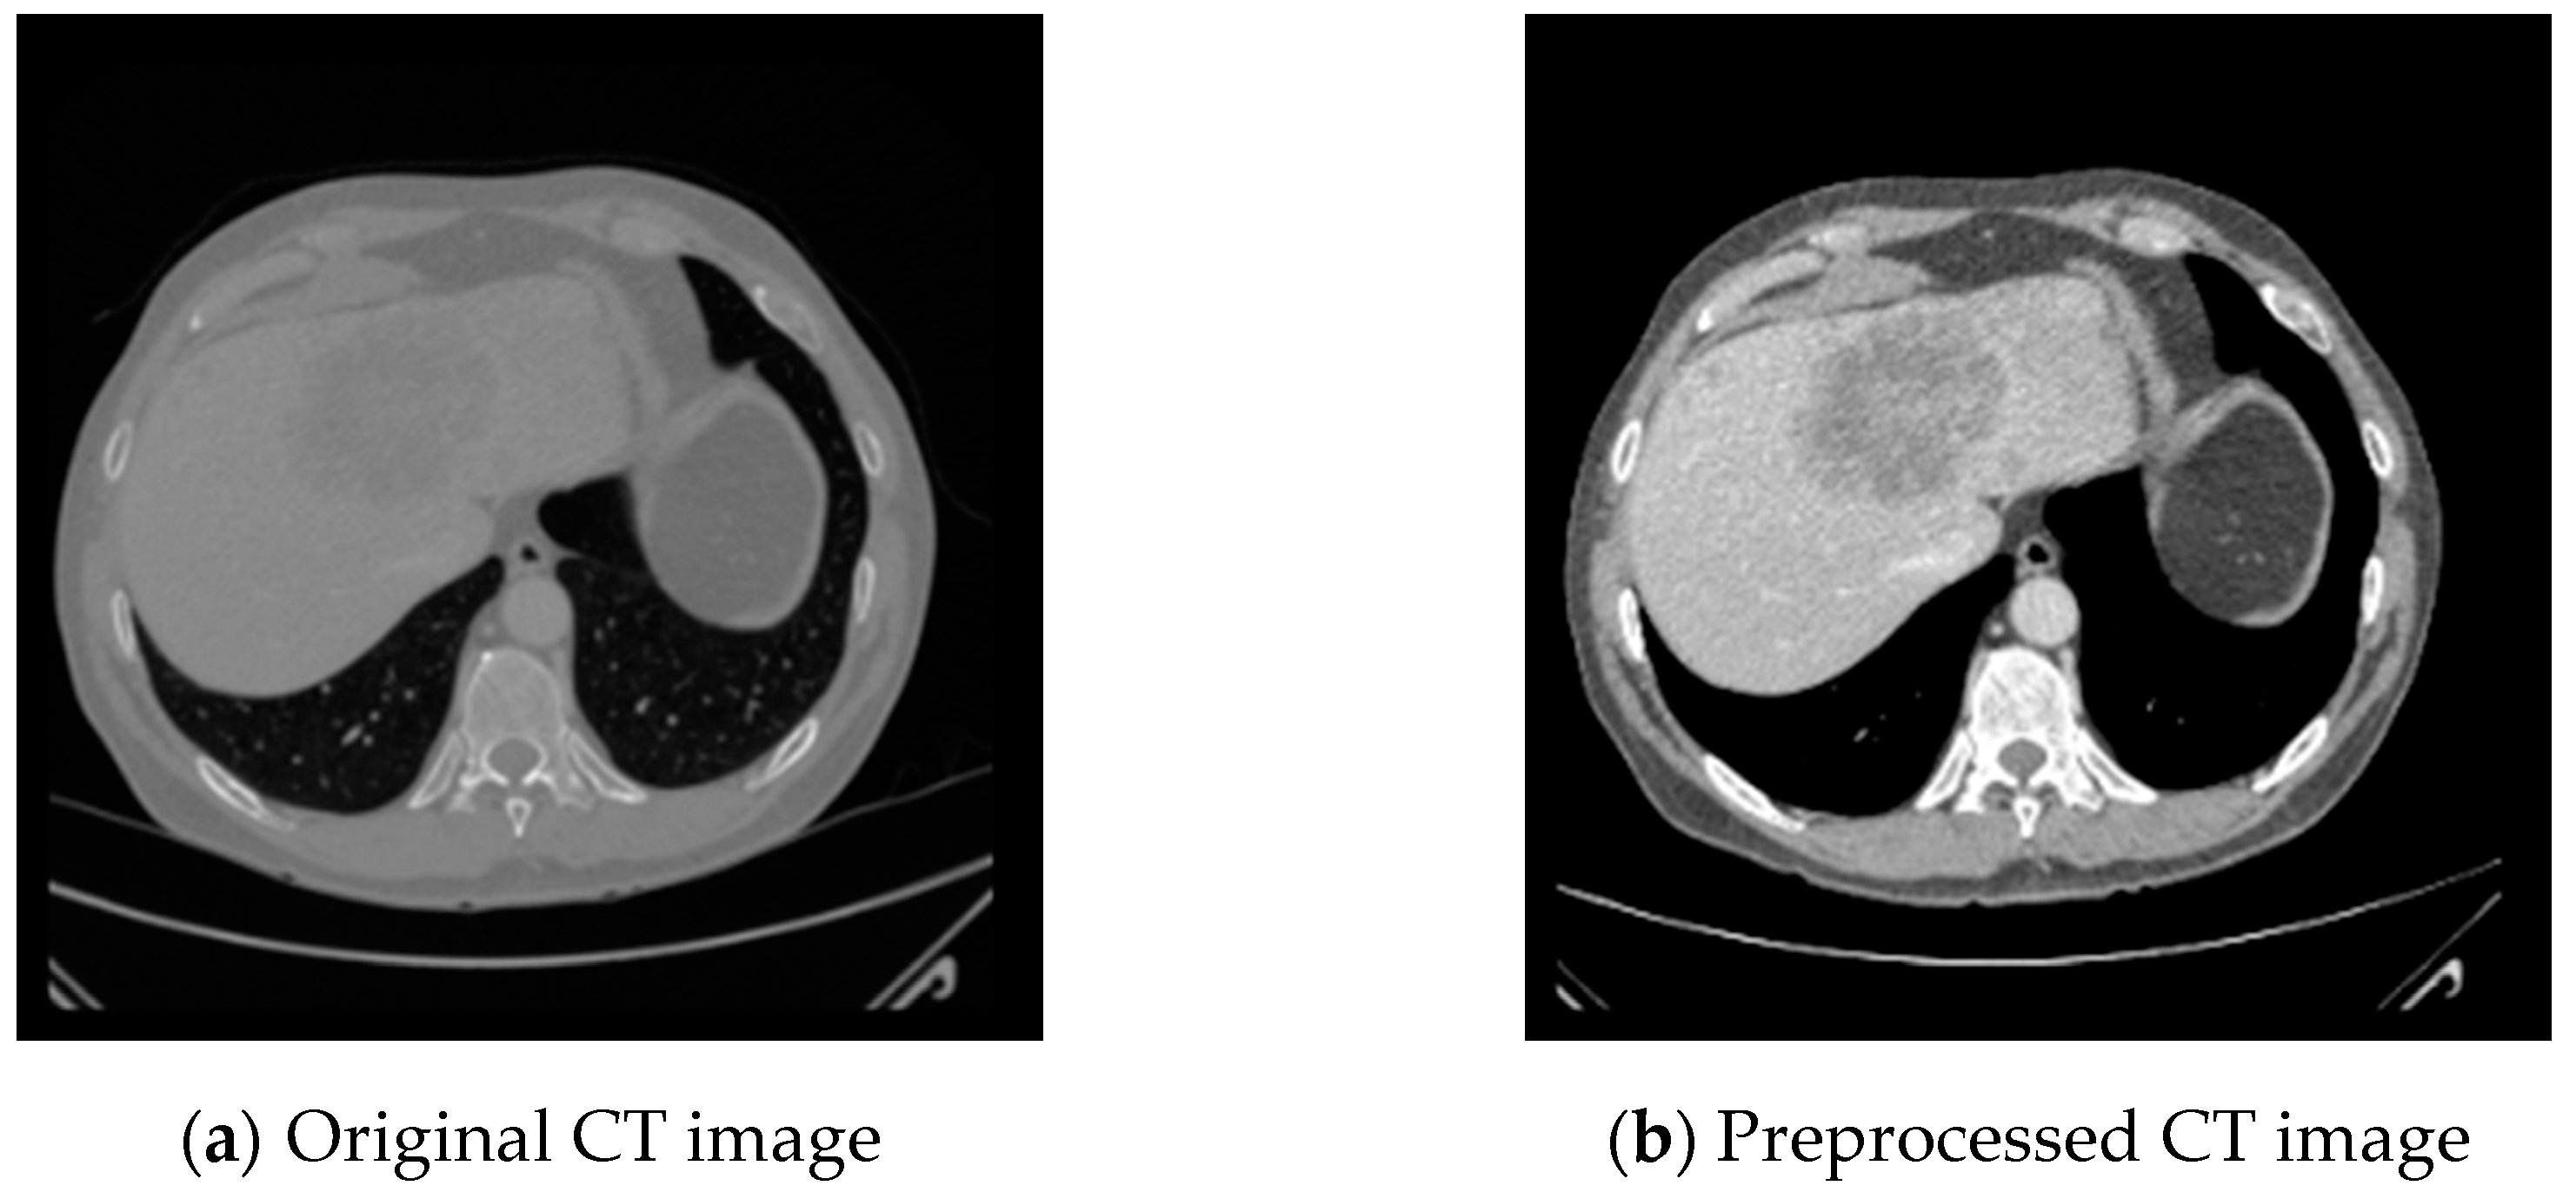

4.2. Data Preprocessing and Augmentation